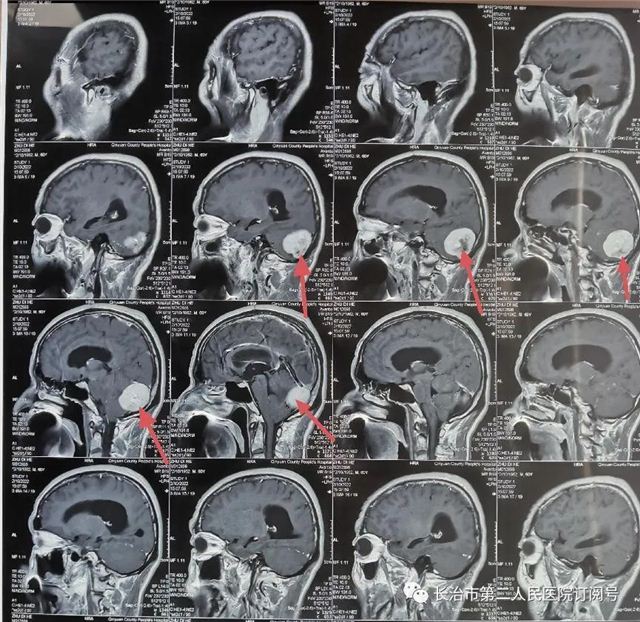

▲术前CT见:后颅窝占位

▲核磁检查见小脑幕下肿瘤,强化明显,考虑脑膜瘤。

(红色箭头为肿瘤)

▲术后复查:肿瘤全切、术野干净未见出血

本病例因幕下空间小,肿瘤压迫小脑,紧邻横窦、窦汇、脑干。手术风险高一旦出血,将危及生命。术后复查肿瘤切除干净,瘤腔未见出血。现患者已痊愈出院。